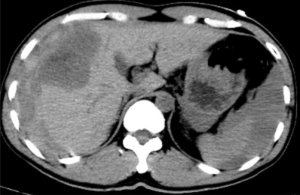

据悉,患者既往有多年乙型肝炎病史,突发右上腹剧烈疼痛入院。患者入院时血压70/40mmHg,心率110次/分,全腹压痛。血常规血红蛋白87g/L,甲胎蛋白>1210 ng/ml。腹部B超检查及CT平扫检查示“肝肿瘤并出血,腹腔积血积液”。